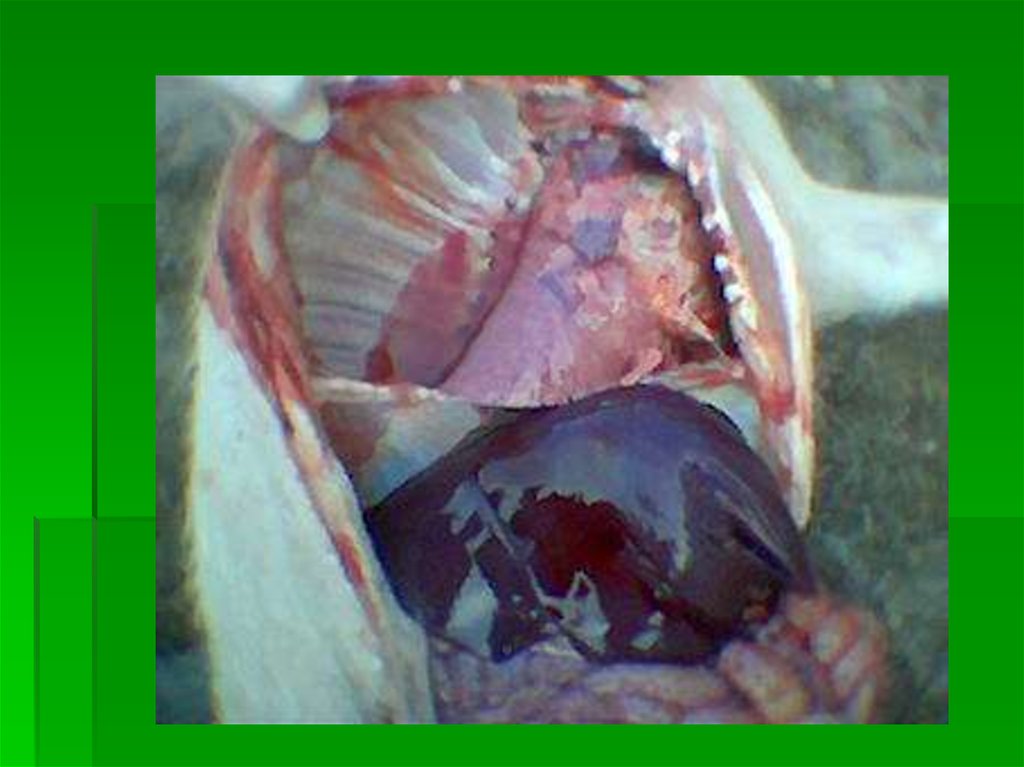

ГЕМОФИЛЕЗ

27. ГЕМОФИЛЕЗ